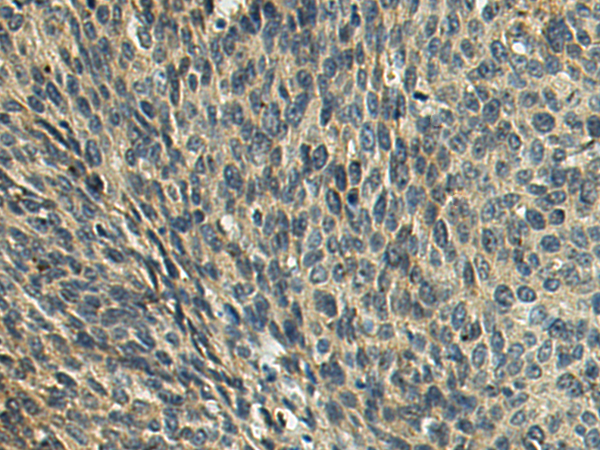

分类: 科研抗体货号: P09847别名:应用: IHC反应种属: Human